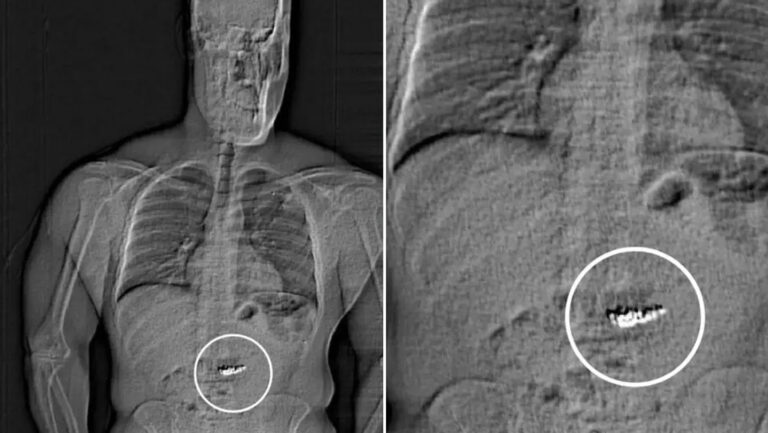

Jaytan Lawrence Gilder, de 32 años, es un ladrón que se tragó pendientes de diamantes valorados en 769 mil dólares, [...]